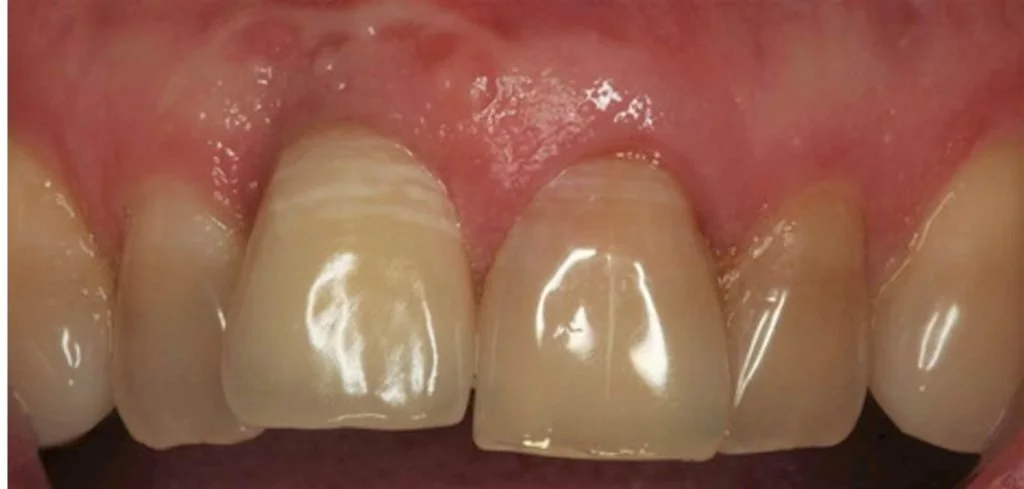

The photo below shows the post operative result one hour after extraction. Note the relative continued eruption (and alveolar bone growth) of the surrounding dentition compared to implant crown 11 placed 20 years ago. This is a common problem when implants are placed in young patients in the aesthetic zone.